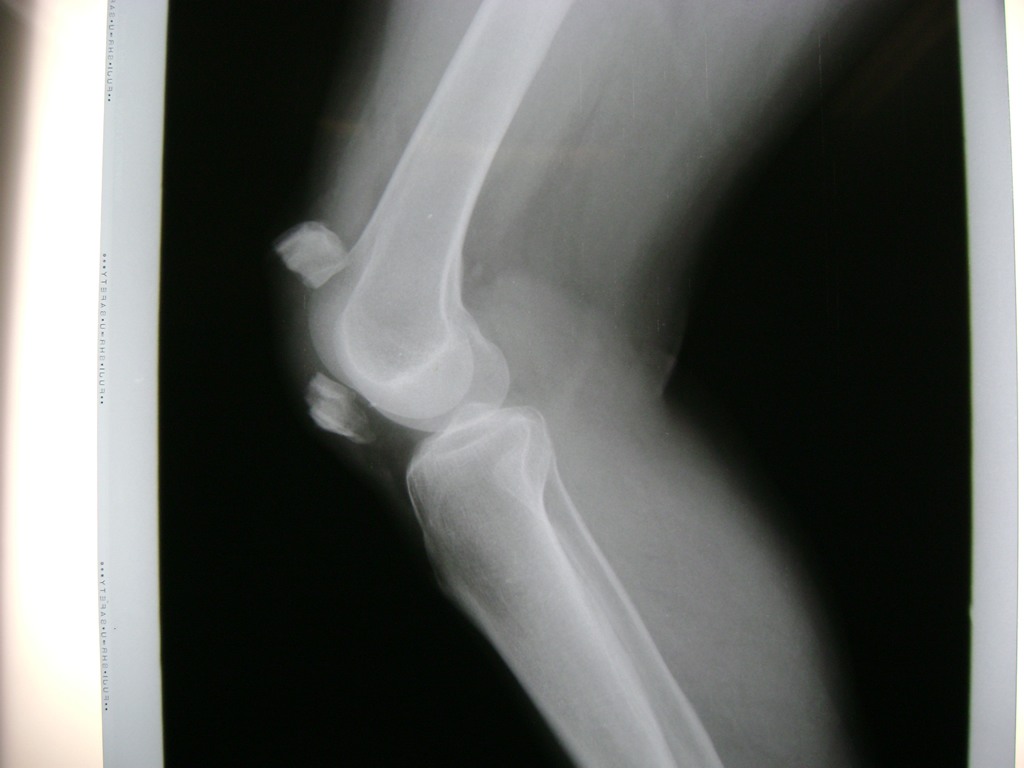

Cirugías de Peroné y Tibia

La artroscopia de rodilla es un cirugía en el cual la estructura interna de la articulación es examinada ya sea para realizar un diagnostico o para realizar un tratamiento, este procedimiento se realiza utilizando un instrumento parecido a un pequeño tubo llamado artroscopio.